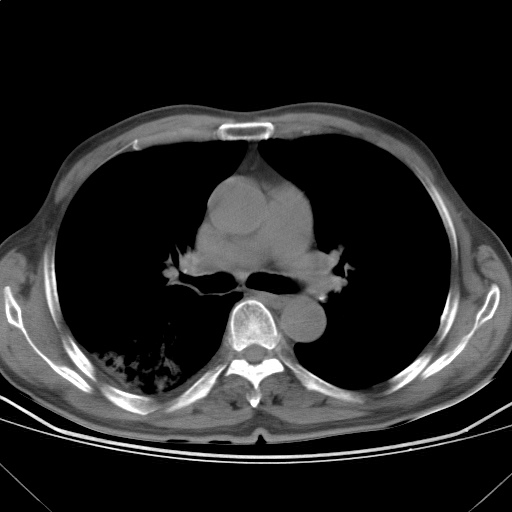

以下是引用随光逐影在2009-5-1 13:53:00的发言:[br]考虑为:1)两肺血行播散型肺结核;2)右肺下叶炎症感染。3)右侧胸膜增厚。